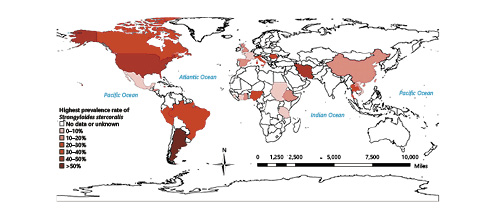

Given the macroscopic appearance of the gastric ulcer and the clinical presentation, neoplastic etiology was suspected, and a CT scan was performed highlighting gastric wall thickness, bronchiectasis, and a spiculated lung nodule with 16 mm in the upper right lobe, which was not previously known (Fig. 3). Imaging with both CT and PET scans excluded lymph node involvement or metastatic disease.

Bronchoscopy with bronchial brushing was performed and was positive for cancer cells, with histological examination revealing squamous cell carcinoma of the lung; the patient was referred to Oncological Pneumology. There was no evidence of filariform larvae in the bronchoalveolar lavage fluid.